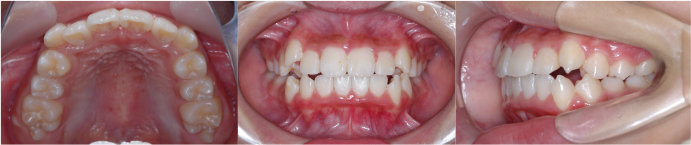

| Case4 |

| 前歯のガタガタ |

| <治療前> |

| <治療後> |

| 主訴 |

上の前歯がガタガタしている |

| 診断名 |

上顎前歯の重度の叢生、下顎前歯の中程度の叢生 |

| 年齢 |

8歳 |

| 使用装置 |

マルチブラケット装置 |

| 抜歯部位 |

永久歯の抜歯は無し |

| 治療期間 |

3年9か月 |

| 治療費概算 |

検査・診断料:5万円+税 装置・技術料:25万円+税 おおよそ1か月ごとの処置・管理料:5,000円+税 保定装置料:5万円+税 |

| リスク・副作用 |

う蝕 |